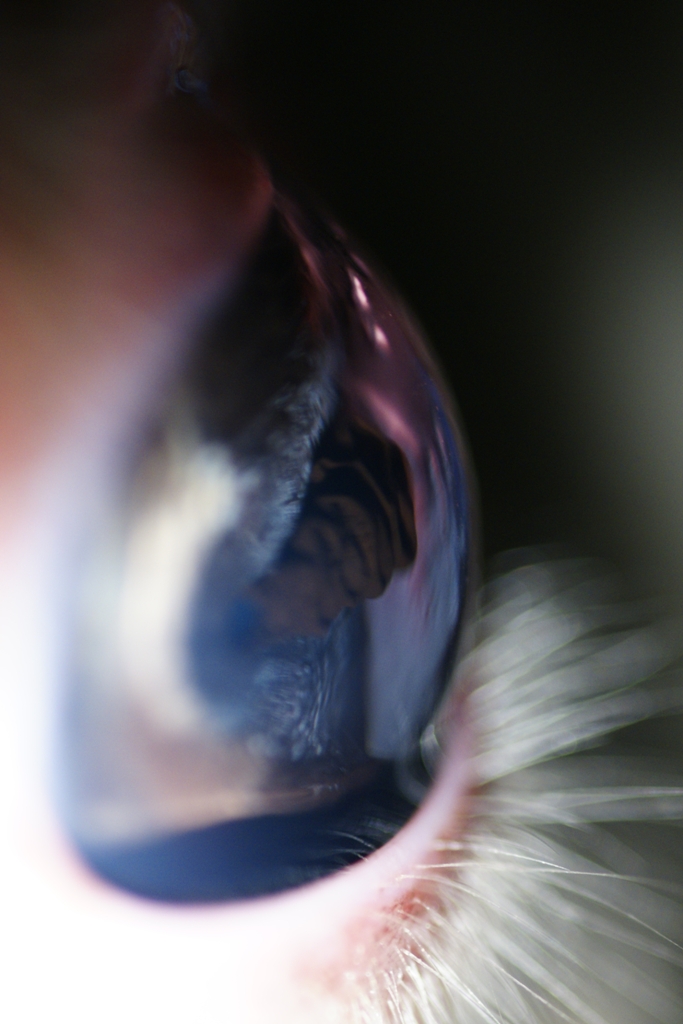

Uvéite antérieure exsudative chez un chat (tous les petits amas sont de la fibrine et traduisent l'inflammation)

- 64533 (353.48 Kio) Consulté 2728 fois